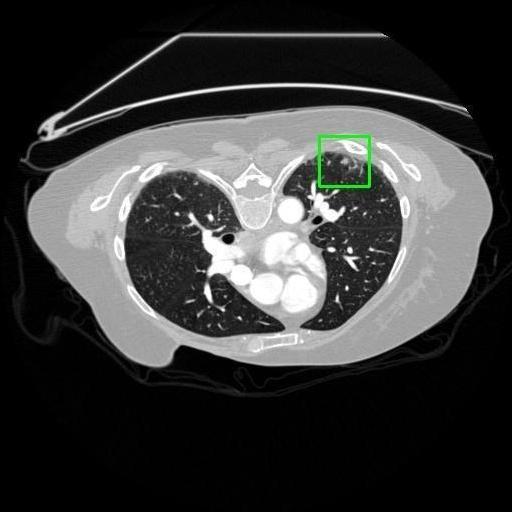

We developed an AI-based system using deep learning models for analyzing lung CT scans to detect and classify pulmonary nodules. We chose the YOLOv11 architecture for its enhanced object detection capability and adapted it specifically for medical imaging, incorporating pixel-level precision and severity classification.

Classification into three severity levels with colored bounding boxes.

Designed a severity classification system that categorizes nodules into null, moderate, and severe using colored bounding boxes, assisting in rapid clinical decision-making.